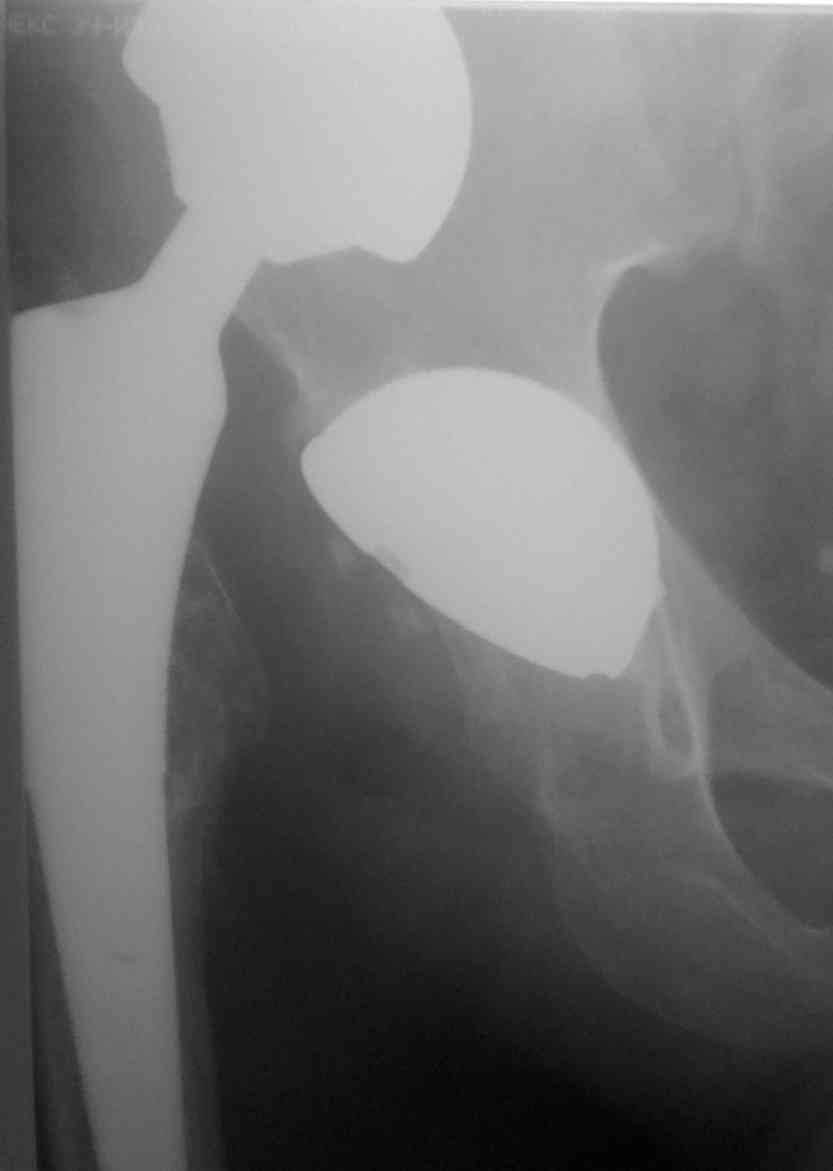

Интересный пример: (см фото)

Вывих эндопротеза на 5 сутки после операции. (причина- ошибки предоперационного планирования и интраоперационные ошибки)

Пациент от ревизии отказался.

Сейчас прошло 4 года после операции. Больной ходит с полной нагрузкой на оперированную конечность с тростью. болей нет.

Извините за плохое качество фото